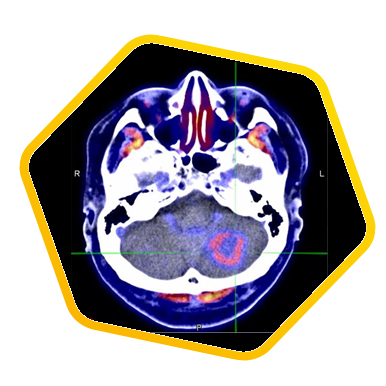

双示踪剂PET/CT (F-18 FDG及Ga-68 DOTATATE) 用於评估脑神经内分泌肿瘤体内的扩散情况

![]() [F-18] FDG |

![]() [Ga-68] DOTATATE |